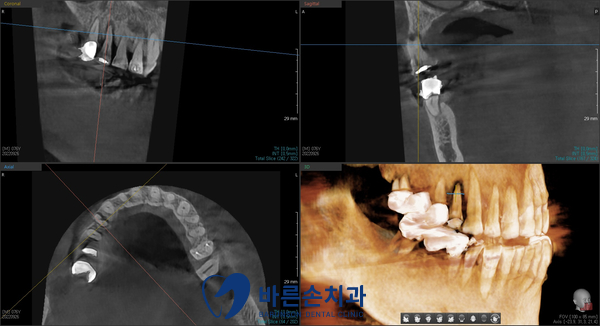

육안상으로 보는 것보다

정확한 진단을 위해 파노라마 사진 및 정밀 3D – CT 촬영을 했습니다

CT 판독 결과 불편감을 호소하는 치아 주변에

염증과 치조골 손상이 있는 것을 알 수 있었습니다

3D- CT 촬영을 한 후

정확한 임플란트 계획을 세웠고